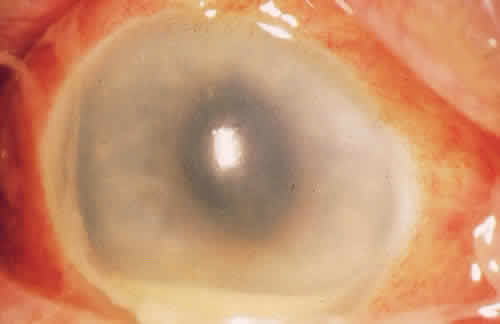

Acanthamoeba species are ubiquitous, free-living, freshwater protozoa that reside in soil, tap water, fresh and brackish seawater, dust, swimming pools, and contact lens cases.67 Contact lens wearers who use homemade saline or who swim with contact lenses account for 85% of patients with Acanthamoeba keratitis (Fig. 11).68 Causes not related to contact lens wear include trauma and topical steroid use. The pain and chemosis are often disproportionate to the normal inflammatory process.8 There may be a radial neurokeratitis, or an opaque circular infiltrate from type III hypersensitivity with immune complex deposition may develop late in the course of the infection. This circle is known as the Wessely immune ring and is also seen in HSV infection (Fig. 12). It has been shown pathologically to be a result of immune complex deposition with local fixation of complement in the cornea and release of pharmacologic agents that cause chemotaxis of polymorphonuclear leukocytes that surround the complexes.20 The Wessely immune ring can also be seen in HSV and fungal keratitis.

Fig. 11. Disciform keratitis from Acanthamoeba infection.

Fig. 12. Wessely immune ring caused by the “zone of optimal proportions” of antibody and antigen (courtesy of Jeffrey Lanier, M.D., Houston, TX).